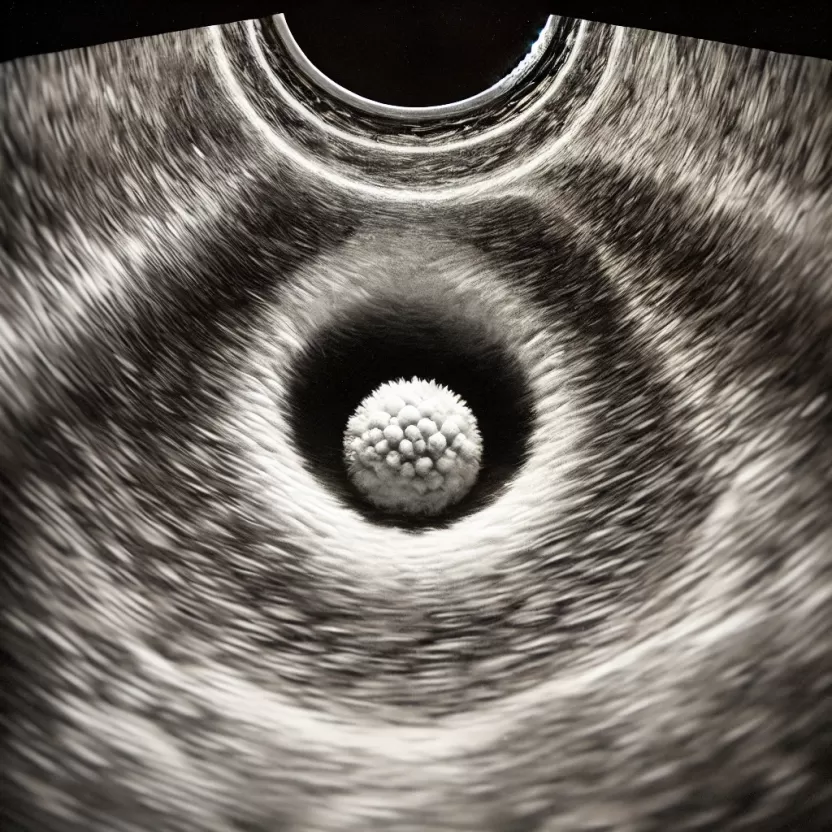

شكل كيس الحمل في السونار المهبلي

كيس الحمل هو غشاء أو هيكل يحيط بالجنين من الخارج، ويظهر قبل ظهور النطفة وهي التي تمثل أول مرحلة من مراحل ظهور ونمو الحنين.

- كيس الجنين يأخذ شكل دائري يزداد قطره وحجمه كلما نما الجنين وتقدم في تطوره، والجدير بالذكر أنه يتم حساب عمر الجنين من خلال قياس كيس الجنين من خلال الفحص المهبلي بواسطة السونار، وهذه الخطوة تبدأ من نهاية الأسبوع الرابع ومع بداية الأسبوع الخامس.